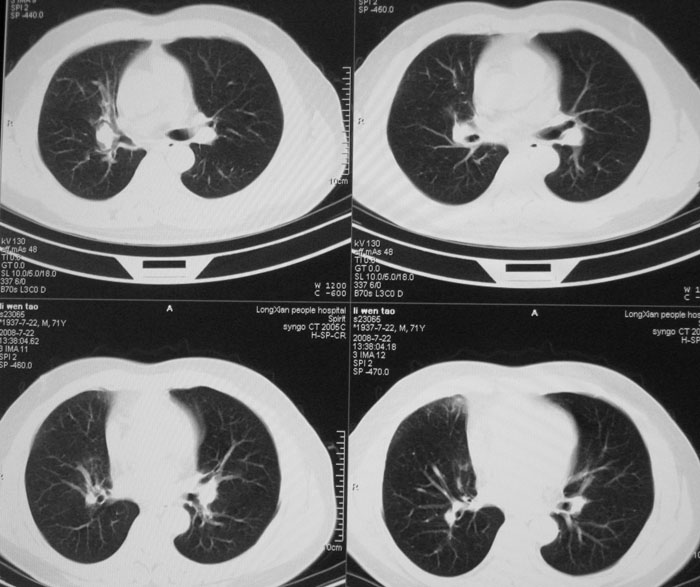

以下是引用光影★笑子在2008-7-27 19:39:00的发言:[br]建议:行支气管镜检查排除肺癌。

以下是引用zhangjixiang在2008-8-6 20:02:00的发言:[br]右主支气管明显变窄伴右上叶尖段不张,结合年龄,考虑右侧中央型肺癌可能性大,纤支镜检可确诊.